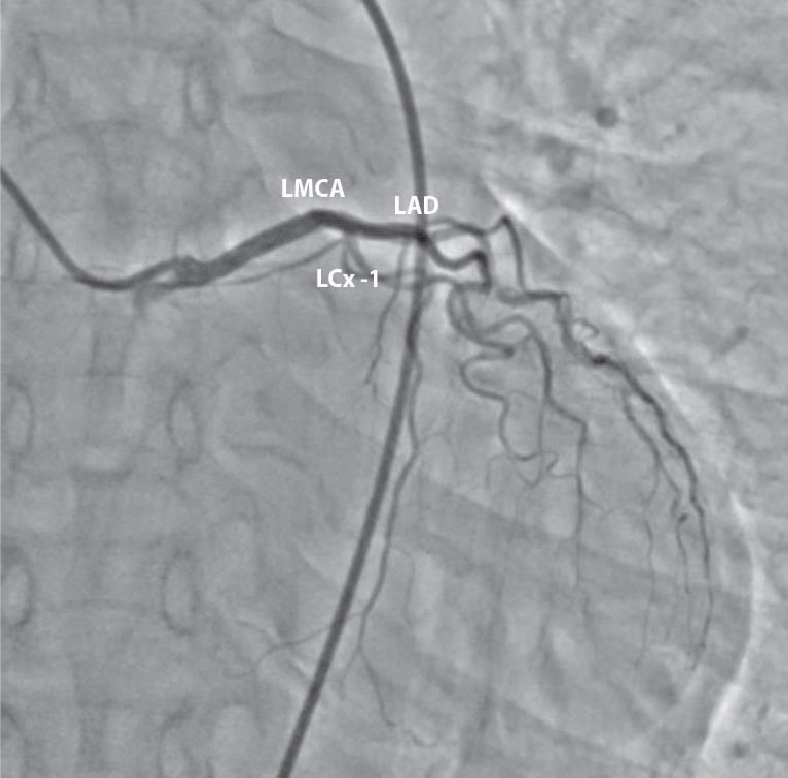

Figure 1. Left coronary angiogram showing small, left circumflex artery (LCx-1) arising from left main coronary artery (LMCA).

Echocardiography revealed hypokinetic inferolateral wall. Elective coronary angiography was then planned, which showed twin LCx arteries: one originating from LMCA and the other from the proximal RCA (Figs. 1 and 2). Patient was discharged on optimal medical therapy and he remained asymptomatic in follow-up period.